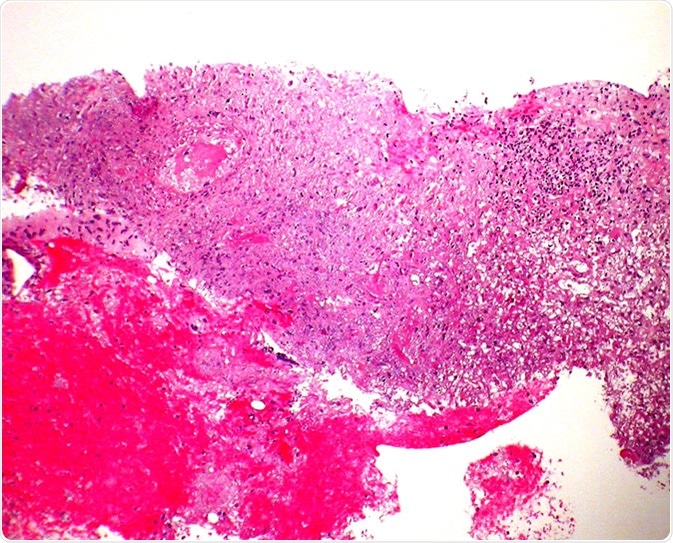

Granulomatosis with polyangiitis (GPA) - Core biopsy Case 190

Granulomatosis with polyangiitis (GPA) - Core biopsy Case 190" by Pulmonary Pathology is licensed under CC BY-SA 2.0

A biopsy (a small tissue sample) from the kidneys or lungs may be ordered to identify signs of inflammation if these are involved.